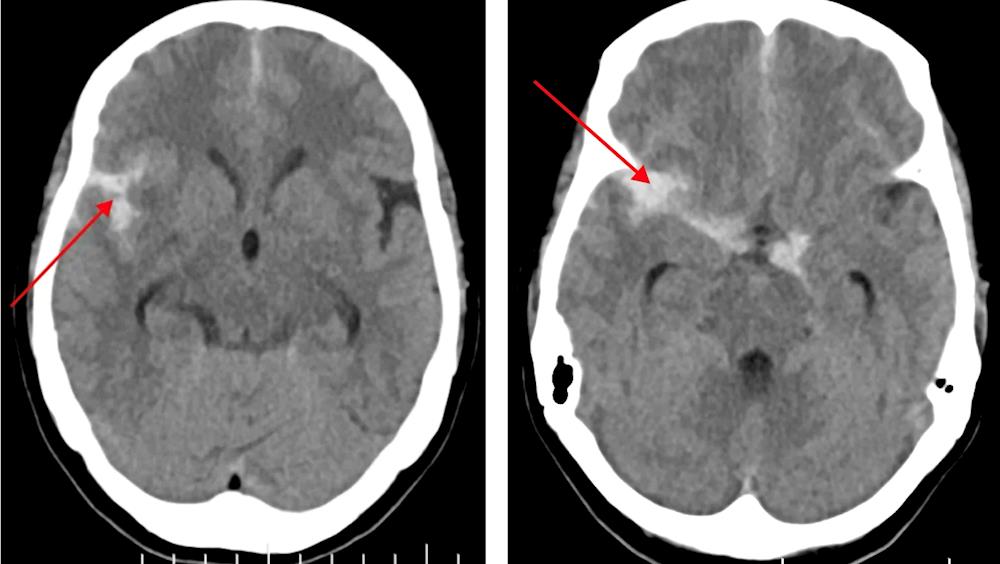

2024年6月19日,家住平马镇的黄阿姨和家人在家中休息,下午15点左右,黄阿姨突然感觉头晕目眩,反胃,恶心呕吐,视物旋转,伴头痛,家人立即送至田东县中医医院急诊科,急诊医生接诊后,考虑脑血管意外,于是立即启动卒中急救绿色通道。急诊头颅CT显示蛛网膜下腔出血,建议行CT血管成像(CTA)进一步检查排除动脉瘤破裂出血。

入院时头颅CT出血灶

经田东县中医医院脑病科技术主任龙少根副主任医师会诊后,收入脑病科住院治疗,龙少根认为患者病情符合行全脑血管造影术(DSA)指征,以进一步明确出血病因。后与患者家属沟通告知行DSA检查必要性和可能存在的风险,征得家属同意,于2024年6月20日行DSA,术中见脑动静脉大致正常,排除微小动脉瘤、颅内血管夹层、烟雾病及其他血管病变。